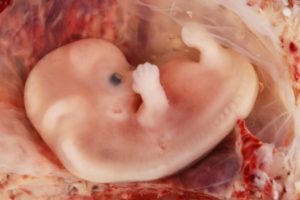

8-10 неделя – одна из критических точек, когда может произойти замершая беременность. Что это и как предотвратить потерю ребенка? Замершая беременность – это гибель плода, которая происходит чаще всего на ранних сроках – до 13 недели.

Наиболее вероятный срок, когда может наступить замершая беременность – 8-9 недель. Это время – одна из критических точек, однако риск сохраняется вплоть до 11 недели, после чего немного снижается. Симптомы замершей беременностиЗамершая беременность означает, что плод прекращает развиваться по каким-то причинам и погибает.

Чаще всего из-за генетических отклонений или не совместимых с жизнью и дальнейшим развитием пороков эмбрион на ранних этапах беременности погибает и перестает развиваться. При этом организм самостоятельно не избавляется от плодного яйца, погибший эмбрион остается в полости матки.

Неразвивающаяся беременность становится результатом остановки в развитии плода, которая обычно происходит в период от начала зачатия и до 28 недели.

Особое внимание стоить уделить, если произошла замершая беременность в 8 недель, причины которой нужно еще узнать. Именно в это время закладываются все жизненно важные органы плода и, если произошло нарушение, природа самостоятельно ликвидирует зародыш во избежание дальнейшей мутации.

Замершая беременность или несостоявшийся выкидыш – это состояние, когда плод прекращает развиваться и гибнет на сроке до 28 недель.

Первые признаки возникшей замершей беременности на раннем сроке возникают, если развитие плода останавливается (замирает), и он погибает. Как правило, замершая беременность в первом триместре наблюдается наиболее часто, и распознать ее можно по определенным признакам.

Прежде всего, отметим, что данная патология представляет собой одну из разновидностей невынашивания плода. Начало такого процесса ничем не отличается от обычного: яйцеклетка, оплодотворенная сперматозоидом, проникает в матку, после чего имплантируется в ней.